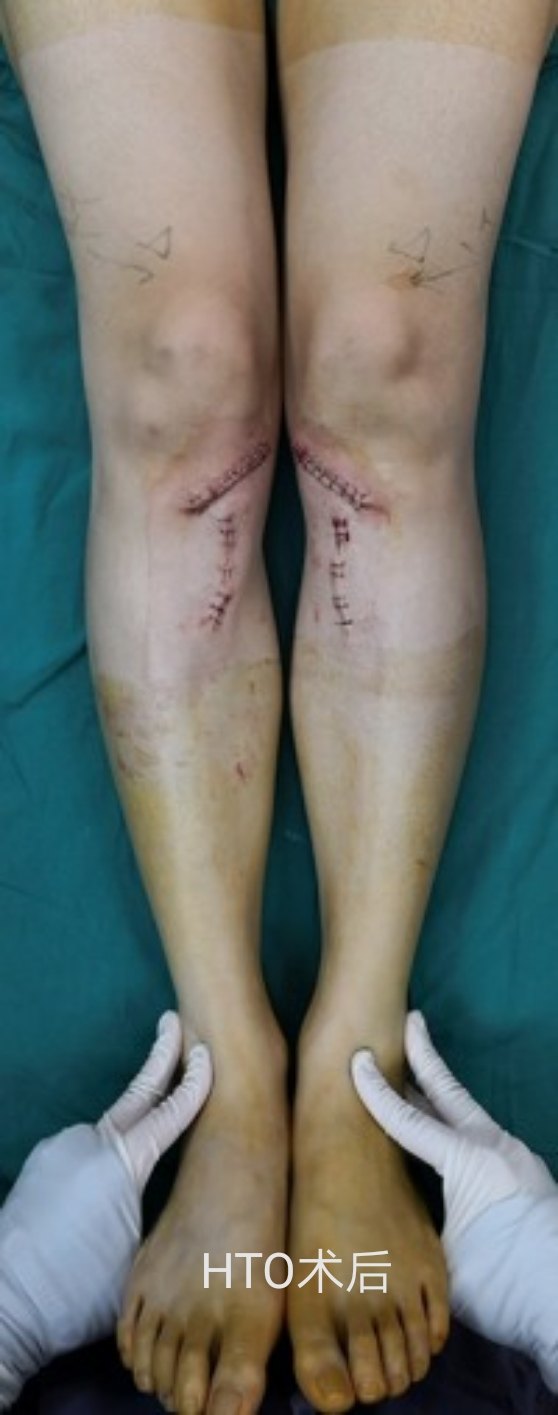

下面就有两种手术的照片,请大家感受了解一下。如果您还有什么疑问,请您毫不犹豫的咨询熊奡大夫吧!